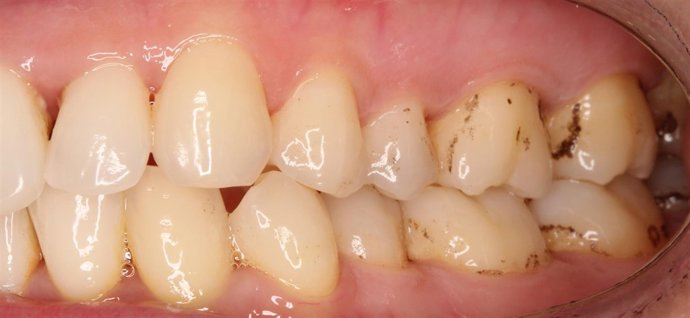

Aspecto De Las Pigmentaciones Negras En El Esmalte Próximo A Las Encías

Investigadores de la CEU UCH han testado la eficacia de la fototerapia antimicrobiana para eliminar las tinciones negras de los dientes en un trabajo publicado por la revista científica 'British Dental Journal Open', del grupo editorial Nature. El estudio ha sido realizado con un dispositivo blanqueador dental de uso doméstico de luz azul de baja intensidad, "demostrando su eficacia al retrasar la reaparición de estas pigmentaciones en el esmalte más cercano a las encías".

En el ámbito odontológico, esta técnica está comenzando a aplicarse en la superficie de los dientes para la eliminación de las bacterias causantes de las pigmentaciones negras extrínsecas en el esmalte. Investigadores de la Universidad CEU Cardenal Herrera de Valencia han aplicado esta técnica a un grupo de pacientes, utilizando un dispositivo blanqueador dental de uso doméstico. Los resultados muestran una reducción del área, el color y la colonización bacteriana de estas manchas negras en la placa dental más próxima a las encías.

Mediante dos únicas sesiones de fototerapia, de ocho minutos de duración cada una, aplicadas a un total de 31 pacientes adultos voluntarios de la Clínica Universitaria Odontológica de la CEU UCH, el equipo investigador ha logrado una reducción de las manchas oscuras, tanto en sus dimensiones como en su tonalidad.